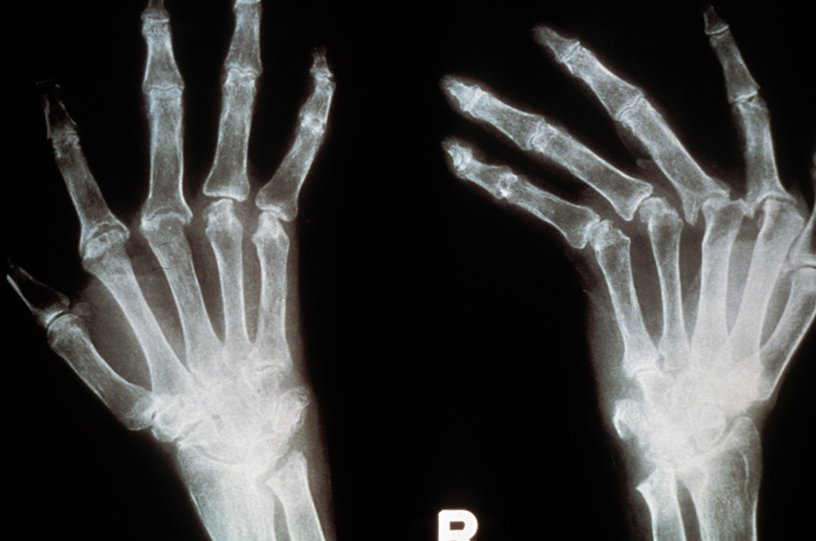

AccueilDossiersPolyarthrite rhumatoïdePolyarthrite rhumatoïde Publié le : 19/06/2023 Temps de lecture : 13 minLa polyarthrite rhumatoïde est une maladie inflammatoire sévère qui touche les articulations. Leur destruction progressive entraîne douleur et handicap. Les traitements ont connu un essor considérable au cours des vingt dernières années. Ils permettent une amélioration notable des symptômes dans la plupart des cas, et même parfois une rémission complète prolongée. Les recherches se poursuivent activement dans le but d’obtenir davantage de rémissions prolongées, notamment via la personnalisation des traitements.Dossier réalisé en collaboration avec Marie-Christophe Boissier, directeur de l’unité Physiopathologie, cibles et thérapies de la polyarthrite rhumatoïde (unité Inserm 1125), Bobigny Table des matièresComprendre la polyarthrite rhumatoïdeDes symptômes typiquesQue se passe-t-il dans une articulation touchée ?Une maladie multifactorielleDes dérèglements immunitaires multiplesLes anomalies du métabolisme énergétiqueL’importance d’un diagnostic précoceTraiter la douleur, l’inflammation, le désordre immunitaireLes traitements ciblésLes enjeux de la rechercheVers des traitements ciblés toujours plus efficacesÉliminer les auto-anticorpsCibler le microbiote ?Des thérapies cellulaires à l’étudeVers des traitements personnalisésNos contenus sur le même sujetActualitésCommuniqués de presseÀ découvrir aussiPour aller plus loinAssociations de patientsComprendre la polyarthrite rhumatoïdeLa polyarthrite rhumatoïde est une maladie auto-immunes qui touche entre 0,5 et 1 % de la population adulte, avec une incidence constante à travers le monde. Si la maladie peut survenir à tout âge, elle apparaît généralement entre 30 et 50 ans, avec un pic autour de 45 ans. Elle est deux à trois fois plus fréquente chez les femmes que chez les hommes, une différence probablement en partie due à un effet des œstrogènes sur la fonction immunitaire.Des symptômes typiquesLa polyarthrite rhumatoïde se manifeste au départ le plus souvent par un enraidissement douloureux et le gonflement de plusieurs articulations, généralement au niveau des poignets, des mains et des doigts. Comme dans beaucoup de maladies inflammatoires, les symptômes sont davantage ressentis en fin de nuit et le matin. L’enraidissement cède au lever, au bout de plusieurs dizaines de minutes (on parle du dérouillage matinal). Une fatigue, une lassitude ou une perte d’appétit accompagne fréquemment les douleurs. C’est à ce premier stade de la maladie que les traitements disponibles sont les plus efficaces et les plus prometteurs sur le long terme.Par la suite, la maladie évolue sous la forme de poussées, entrecoupées de rémissions plus ou moins complètes. Toutes les articulations peuvent alors être touchées : coudes, épaules, cou, pieds et orteils, genoux, hanches. Rapidement, ces articulations commencent à s’altérer : des « pincements » des cartilages, la destruction des os voisins ou encore des luxations deviennent alors visibles par radiographie. Au bout de plusieurs années d’évolution, la polyarthrite rhumatoïde finit par provoquer des déformations articulaires et des destructions des tendons. La chirurgie orthopédique est alors nécessaire pour réparer, et souvent remplacer les articulations par des prothèses. Main d’un patient souffrant de polyarthrite rhumatoïde © Inserm/Cantagrel, AlainLa polyarthrite rhumatoïde est souvent associée à d’autres maladies auto-immunes. Parmi les plus fréquentes, citons celles qui s’attaquent aux glandes salivaires et lacrymales (syndrome de Gougerot-Sjögren), à la thyroïde (thyroïdite de Hashimoto) ou au pancréas (diabète). Les accidents vasculaires (angine de poitrine, infarctus du myocarde, accidents vasculaires cérébraux) sont également plus fréquents en cas de polyarthrite rhumatoïde qu’en population générale.Il faut souligner que la polyarthrite rhumatoïde est une maladie grave qui entraîne une surmortalité. Les causes les plus fréquentes de décès prématuré des patients sont des maladies cardiovasculaires, dont la survenue est favorisée par la combinaison de facteurs de risque comme l’hypertension et la dyslipidémie avec l’inflammation chronique. En outre, un dysfonctionnement microvasculaire est observé chez certains patients, à l’instar de celui observé chez les diabétiques : il constitue un facteur de risque supplémentaire. Mais en réduisant l’inflammation, les traitements de la polyarthrite rhumatoïde atténuent ces risques.Que se passe-t-il dans une articulation touchée ?Une articulation saine comporte du cartilage et une membrane qui tapisse tous les tissus (ligaments, tendons, capsules) unissant les extrémités osseuses : la membrane synoviale. La polyarthrite rhumatoïde se caractérise par une inflammation de cette membrane. On parle de synovite agressive.La maladie débute des années avant l’apparition des symptômes. On observe d’abord la présence de quelques cellules immunitaires impliquées dans l’inflammation, la multiplication des vaisseaux, puis un épaississement considérable du tissu synovial pour former ce que l’on appelle un « pannus » synovial. La membrane comporte alors de nombreuses couches au lieu d’une seule, et le tissu synovial et sous-synovial est infiltré par de très nombreuses cellules immunitaires qui vont conduire à la destruction des structures alentours : le cartilage s’érode et s’amincit, l’os au sein duquel apparaissent des encoches ou des cavités (« géodes ») se déminéralise tout autour de l’articulation. Rapidement, les tendons et les ligaments peuvent être aussi attaqués et se rompre.Une maladie multifactorielleL’apparition de la polyarthrite rhumatoïde résulte de l’interaction de facteurs génétiques et d’expositions environnementales spécifiques. Le facteur de risque le plus important est génétique, avec un risque multiplié par 2 à 5 pour les personnes qui ont un parent atteint. Une centaine de gènes de prédisposition a été identifiée. Situés dans différentes régions du génome, ils jouent tous un rôle dans l’immunité. Des variants des gènes du complexe majeur d’histocompatibilité (HLA-DR) ont une implication bien plus forte que les autres gènes de prédisposition. Ils permettent la synthèse de protéines qui présentent une affinité particulière pour des molécules appelées « antigènes citrullinés », qui jouent un rôle primordial dans le dysfonctionnement immunitaire qui caractérise la maladie (voir plus loin).Toutefois, des études conduites sur des jumeaux homozygotes (les « vrais jumeaux », qui portent le même patrimoine génétique) montrent que si l’un est atteint, l’autre ne le sera que dans 10 à 15 % des cas, ce qui indique clairement que d’autres facteurs interviennent.Il s’agit d’un ensemble de facteurs environnementaux qui peuvent accroître le risque de désordre immunologique en modifiant l’expression de certains gènes, notamment par des mécanismes épigénétiques. Parmi eux, le tabagisme joue un rôle important : la polyarthrite rhumatoïde est plus fréquente, plus grave, et répond moins bien au traitement chez les fumeurs. De plus, le tabagisme et le risque génétique sont synergiques : le risque de développer la maladie est jusqu’à 20 fois plus grand chez les fumeurs que chez les non-fumeurs qui présentent des marqueurs génétiques identiques. Néanmoins, le risque associé au tabac diminue progressivement lorsqu’on arrête de fumer, se rapprochant de celui observé chez les non-fumeurs au bout de deux à trois décennies.L’exposition à la pollution atmosphérique semble constituer un autre facteur de risque : particules fines, poussières, silice sont suspectées. Par ailleurs, certains agents infectieux ont également été incriminés, comme le virus d’Epstein-Barr ou les bactéries P. gingivalis et A. actinomycetemcomitans. Mais aucune étude n’a donné de résultat généralisable.D’autres facteurs augmentent légèrement le risque de polyarthrite rhumatoïde, comme l’obésité, un faible taux de vitamine D et l’utilisation de contraceptifs oraux. Enfin, il existe également des facteurs qui diminuent ce risque, en particulier l’adoption d’un régime méditerranéen ou la consommation d’acides gras oméga‑3.Des dérèglements immunitaires multiplesLa polyarthrite rhumatoïde est une maladie auto-immune liée à des dérèglements dans le fonctionnement du système immunitaire des patients, qui va s’attaquer à des cellules saines de leur organisme, principalement au niveau des articulations, mais pas uniquement.Des auto-anticorps nommés anti-CCP (pour anti-cyclic citrullinated peptides) ou ACPA (pour anti citrullinated peptides antibodies) sont présents chez environ 70 % des patients. Ils reconnaissent des petits fragments de protéines naturellement présents dans l’organisme, qui contiennent un acide aminé appelé citrulline. En se fixant sur des protéines citrullinées au niveau de l’articulation, ces auto-anticorps participent à la destruction osseuse et articulaire. Ils peuvent être détectés dans le sang des patients en moyenne 4,5 ans avant le début des symptômes.Plusieurs types de cellules immunitaires sont par ailleurs impliqués dans l’inflammation et la destruction des tissus qui caractérisent la polyarthrite rhumatoïde : des lymphocytes B et T, des macrophages ou encore des cellules dendritiques. Chez les patients atteints, les lymphocytes T régulateurs qui contrôlent habituellement la réponse immunitaire présentent par exemple une activité insuffisante. Et de nombreuses autres populations lymphocytaires se comportent de façon anormale, exerçant leur activité de façon aléatoire. La nature des cellules immunitaires présentes dans les articulations des patients et les fonctions qu’elles y exercent sont hétérogènes, suggérant l’existence de différentes voies biologiques impliquées dans la maladie.Le système immunitaire inné s’active également de façon aberrante. Des molécules pro-inflammatoires de la famille de cytokines (interleukines, TNF-alpha...) sont produites en abondance. S’ensuit une réaction inflammatoire chronique. Ces cytokines contribuent en outre à la stimulation de la synthèse de molécules toxiques par des cellules présentes dans l’articulation, conduisant à la destruction des tissus articulaires.L’inflammation peut également toucher d’autres tissus ou organes, comme les vaisseaux sanguins, les ganglions lymphatiques, les muqueuses, le poumon, le cœur, le tractus gastro-intestinal ou encore la cavité buccale. La plupart des patients présente par exemple des anomalies dans le tissu pulmonaire, le plus souvent asymptomatiques mais pouvant évoluer vers des essoufflements. Par ailleurs, environ un tiers des malades développent des nodules rhumatoïdes : il s’agit de formations indolores et bénignes de consistance ferme, en général localisées sous la peau.Les anomalies du métabolisme énergétiqueLa polyarthrite rhumatoïde est également une maladie du métabolisme énergétique. En effet, l’inflammation génère une hypoxie, c’est-à-dire un déficit en oxygène nécessaire au fonctionnement des cellules de l’organisme. Pour s’adapter à cet environnement, les cellules des articulations malades modifient leur fonctionnement, notamment pour continuer à former de nouveaux vaisseaux. Ces adaptations métaboliques provoquent la synthèse de composés pro-inflammatoires comme le lactate et le succinate, qui aggravent encore l’inflammation.L’importance d’un diagnostic précoceDans la polyarthrite rhumatoïde comme dans bien d’autres maladie, un traitement est plus efficace s’il est démarré à un stade précoce. En cas de douleurs ou de gonflements articulaires, mieux vaut consulter sans attendre. Le médecin cherchera d’éventuelles autres atteintes des articulations, de la colonne vertébrale, de la peau (psoriasis), de muqueuses ou d’organes internes comme le tube digestif.Le diagnostic repose sur : Un interrogatoire et un examen cliniqueDes examens d’imagerie médicale : radiographies des mains, des pieds, des articulations touchées et souvent du rachis (colonne vertébrale), à la recherche d’une synovite et de son potentiel destructeur (déminéralisation, pincement articulaire). Une échographie ou une IRM est parfois pratiquée.Des analyses biologiques : mesure de marqueurs d’inflammation (vitesse de sédimentation et dosage de la protéine C réactive) et recherche de la présence d’auto-anticorps ACPA ainsi que d’un autre anticorps appelé « facteur rhumatoïde ». La détermination du génotype HLA-DR est utilisée par certaines équipes.Radiographie de mains de patient atteint de polyarthrite rhumatoïde, déviation cubitale © Inserm/Cantagrel, AlainTraiter la douleur, l’inflammation, le désordre immunitaireTout au cours de l’évolution de la polyarthrite rhumatoïde, il faut lutter contre la douleur associée. Mais dans cette maladie, il est parfois illusoire de viser la disparition de toute douleur, sauf au prix d’une escalade thérapeutique. Le dialogue médecin-malade est donc nécessaire pour identifier le seuil douloureux résiduel acceptable. L’antalgique de base reste le paracétamol. Les antalgiques plus puissants comportent des effets secondaires dont il faut bien évaluer les inconvénients avant toute prescription dans le cadre d’une maladie chronique.Pour réduire l’inflammation, les corticoïdes sont souvent utilisés car ils sont efficaces même à faibles doses. Ils sont toutefois prescrits avec plusieurs précautions (surveillance du régime, de la pression artérielle, du métabolisme, des os), et l’idéal est de pouvoir les arrêter grâce aux autres traitements, ce qui n’est pas toujours possible. Leur injection directement dans l’articulation peut également être proposée en cas d’atteinte tenace. Et dans quelques cas, leur administration par perfusion peut être nécessaire.Pour faire face au désordre immunitaire, l’administration d’un immunosuppresseur est le traitement de première intention. Il s’agit presque toujours du méthotrexate, en prise hebdomadaire en l’absence de contre-indication (dont la grossesse). Entre 25 et 40 % des patients sont efficacement soulagés par ce traitement. En cas de contre-indications, le méthotrexate peut être remplacé par le leflunomide ou, très rarement, par la salazopyrine. La surveillance instaurée dès que le traitement est mis en route permet de s’assurer qu’il est bien toléré par le patient et qu’il est efficace. Pour en estimer le bénéfice, on utilise le DAS28, un score d’activité de la maladie qui prend en compte le nombre d’articulations douloureuses et d’articulations gonflées, une évaluation chiffrée de la douleur ressentie par le malade, ainsi que la vitesse de sédimentation en tant que marqueur de l’inflammation. Les traitements ciblésLorsque le méthotrexate n’apporte pas un soulagement suffisant après quelques mois, que la maladie est active ou que la destruction des articulations progresse, la prescription d’un traitement ciblé est nécessaire. C’est souvent le cas.Ces traitements agissent chacun sur un acteur précis du processus inflammatoire. Ils entraînent une réponse favorable dans les trois quarts des cas, et même une rémission prolongée dans un quart des cas. Lorsque l’un d’eux n’est pas efficace, c’est le plus souvent en raison du développement d’anticorps dirigés contre la molécule thérapeutique. Mais il est possible de rechercher et de doser ces anticorps pour adapter le traitement : si leur présence est avérée ou en cas d’inefficacité inexpliquée d’un de ces médicaments, il faut changer de molécule.Les traitements ciblés de la polyarthrite rhumatoïde actuellement disponibles appartiennent aux familles suivantes : Les anti-TNF-alpha : il s’agit d’anticorps monoclonaux dirigés contre la cytokine TNF-alpha, ou bien de protéines solubles qui miment le récepteur de cette cytokine et la capturent ainsi.Les anti-IL‑6 : ceux qui sont actuellement disponibles ciblent le récepteur de l’interleukine‑6, mais des traitements ciblant la cytokine elle-même sont en cours de développementLes anti-CD20 : il s’agit d’anticorps monoclonaux qui permettent d’éliminer les lymphocytes B exprimant CD-20 à leur surface, qui produisent des auto-anticorps.CTLA4-Ig : cette molécule limite l’activation des lymphocytes T en bloquant une protéine (CTLA‑4) exprimée à leur surface.Les anti-JAK : ils ciblent une protéine intracellulaire (JAK), exprimée par un grand nombre de cellules immunitaires. En découle, une baisse de la production de cytokines pro-inflammatoires comme le TNF-alpha. Ils sont disponibles sous forme de comprimés oraux (alors que les autres thérapies ciblées doivent être injectées) mais sont soumis à davantage de restrictions de prescription (âge, poids, facteurs de risque cardiovasculaires…)Les thérapies ciblées sont le plus souvent très bien tolérées. Elles réduisent les défenses immunitaires des patients, mais sont associées à de faibles taux d’infections graves. La possibilité d’arrêter les traitements lorsque la maladie est bien contrôlée a été testée dans différentes études : si cette stratégie fonctionne chez de rares patients, le risque de rechute est majeur, avec la possibilité que les mêmes médicaments ne soient pas aussi efficaces par la suite. Les enjeux de la rechercheVers des traitements ciblés toujours plus efficacesLa recherche visant à mettre au point de nouveaux traitements contre la polyarthrite rhumatoïde est très active grâce à l’identification de nombreuses cibles potentielles : molécules d’activation des macrophages, des polynucléaires, cytokines de l’inflammation ou de l’angiogenèse, d’autres molécules de signalisation… Les succès déjà obtenus, qui ont pu être appliqués à d’autres maladies chroniques comme la maladie de Horton, la maladie de Crohn ou encore le psoriasis, ont fait de cette maladie articulaire un modèle pour la recherche sur le traitement de l’inflammation chronique.Des laboratoires tentent par ailleurs de développer des molécules thérapeutiques plus efficaces, agissant sur des cibles déjà exploitées, par exemple sur l’interleukine‑6.Éliminer les auto-anticorpsPour réduire la charge d’auto-anticorps ACPA présents chez les patients, des chercheurs travaillent sur l’aphérèse. Il s’agit d’une technique de filtration du sang qui permet de piéger les ACPA en les mettant en contact ex vivo avec leur cible (des protéines citrullinées). Un essai clinique est prévu dans les hôpitaux de Marseille.Cibler le microbiote ?Les travaux sur le microbiote, l’ensemble des bactéries qui colonisent l’organisme, pourraient également permettre des développements thérapeutiques. Des anomalies du microbiote intestinal associées à la polyarthrite rhumatoïde ont été mises en évidence, en particulier une diminution de la diversité microbienne et de la quantité des Firmicutes, des bactéries connues pour leurs propriétés immunorégulatrices. Corriger ces anomalies pourrait apporter un bénéfice aux patients.La composition du microbiote buccal est également scrutée en raison de la fréquence de périodontite sévère chez les patients atteints de polyarthrite rhumatoïde ou encore de la présence d’ADN de Porphyromonas gingivalis dans le liquide synovial de certains d’entre eux.Des thérapies cellulaires à l’étudePlusieurs approches de thérapies cellulaires sont en développement. Elles consistent toutes à greffer de cellules thérapeutiques au niveau des articulations atteintes.L’utilisation de cellules souches mésenchymateuses a fait l’objet de plusieurs études précliniques et cliniques. Ces cellules produisent des molécules qui améliorent le contrôle de l’inflammation et peuvent se différencier en cellules de l’os et du cartilage, favorisant leur régénération. Le traitement est bien toléré et apporte un certain bénéfice jusqu’à trois ans après l’injection. L’effet semble renforcé par la co-administration d’IFN-gamma. Le développement de cette stratégie se poursuit.Une autre approche repose sur l’administration de cellules T régulatrices (Treg) qui améliorent le contrôle de l’inflammation.Enfin, les cellules CAR‑T utilisées dans le traitement du cancer sont à l’essai. Il s’agit de prélever des lymphocytes T du patient et de les armer génétiquement pour leur permettre de reconnaitre et d’éliminer spécifiquement des molécules spécifiques, en particulier les auto-anticorps ACPA largement impliqués dans la pathologie.Vers des traitements personnalisésIl n’est pas encore possible de prédire l’efficacité d’un médicament immunosuppresseur, ce qui expose les patients à des traitements potentiellement inutiles et à leurs effets indésirables. Des études visant à identifier les patients qui sont susceptibles de répondre à un traitement ciblé particulier sont donc menées. Il a notamment été constaté que d’un patient à l’autre, il existe une grande hétérogénéité dans les cellules et les molécules présentes dans les articulations malades. Cependant, à ce jour, aucune combinaison de biomarqueurs, d’analyses tissulaires ou de marqueurs génétiques qui permettrait d’améliorer la prise en charge des patients en facilitant le choix d’un traitement n’a été identifiée. Nos contenus sur le même sujetActualités14/10/19 Des cellules à deux X favoriseraient la polyarthrite rhumatoïde chez les hommes06/10/14 Une cible unique pour traiter les maladies auto-immunesCommuniqués de presse22/10/18 Identification d’un facteur génétique à l’origine de la fibrose pulmonaire qui complique la polyarthrite rhumatoïde04/10/16 1 Français sur 2 souffre de douleurs articulaires03/02/16 Ostéoporose : comment préserver l’équilibre entre formation et destruction de l’os ?À découvrir aussiArticulations : Des rouages vitaux à mieux protéger, dossier Grand angle du magazine de l’Inserm n°56 (mars 2023)Réparer le cartilage – dossier d’information Maladies auto-immunes – dossier d’informationPour aller plus loinPolyarthrite rhumatoïde évolutive grave – Haute autorité de santéPolyarthrite rhumatoïde en 100 questions – Assistance Publique-Hôpitaux de ParisPolyarthrite rhumatoïde – Société française de rhumatologiePolyarthrite rhumatoïde – Assurance maladieAssociations de patients Association française de lutte anti-rhumatismale (AFLAR)Association française des polyarthritiques et des rhumatismes inflammatoires chroniques (AFP)Association nationale de défense contre la polyarthrite rhumatoïde (ANDAR)Association pour les enfants atteints d’arthrite juvénile idiopathique et autres maladies chroniques rhumatismales (KOURIR)Fondation Arthritis